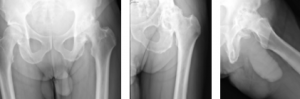

Case Report #1

John Aldridge, MD

Hampton Roads Orthopedics and Sports Medicine

A 67-year-old Caucasian female weighing 190lbs diagnosed with osteo/degenerative arthritis received Advita’s Alteon® Neck Preserving Stem with a Biolox®delta femoral head and Novation® Crown Cup acetabular shell. The patient went under general anesthesia using a direct anterior surgical approach with an incision size of 10cm. There was an estimated blood loss of 150cc and surgery duration was 41 minutes. The patient was discharged after one day postoperative with a walker to in-home care for rehabilitation.

Pre-Op AP Pelvis

Harris Hip Score 37 (max=100) | Oxford Hip Score 19 (max=48)

6-Week Post-Op

Harris Hip Score 98 (max=100) | Oxford Hip Score N/A

3-Month Post-Op

Harris Hip Score 94 (max=100) | Oxford Hip Score 43 (max=48)

1-Year Post-Op

Harris Hip Score 100 (max=100) | Oxford Hip Score 48 (max=48)

CONCLUSION

Before surgery, this patient presented low Harris Hip and Oxford Hip scores. Once she reached her one-year follow up, her scores increased by more than 63.0 percent on the Harris Hip and 60.4 percent on the Oxford Hip. The patient is satisfied with her total hip replacement with the direct anterior approach, which has been associated with faster functional recovery than the posterolateral approach. The outcomes of her surgery continue to be followed annually. •